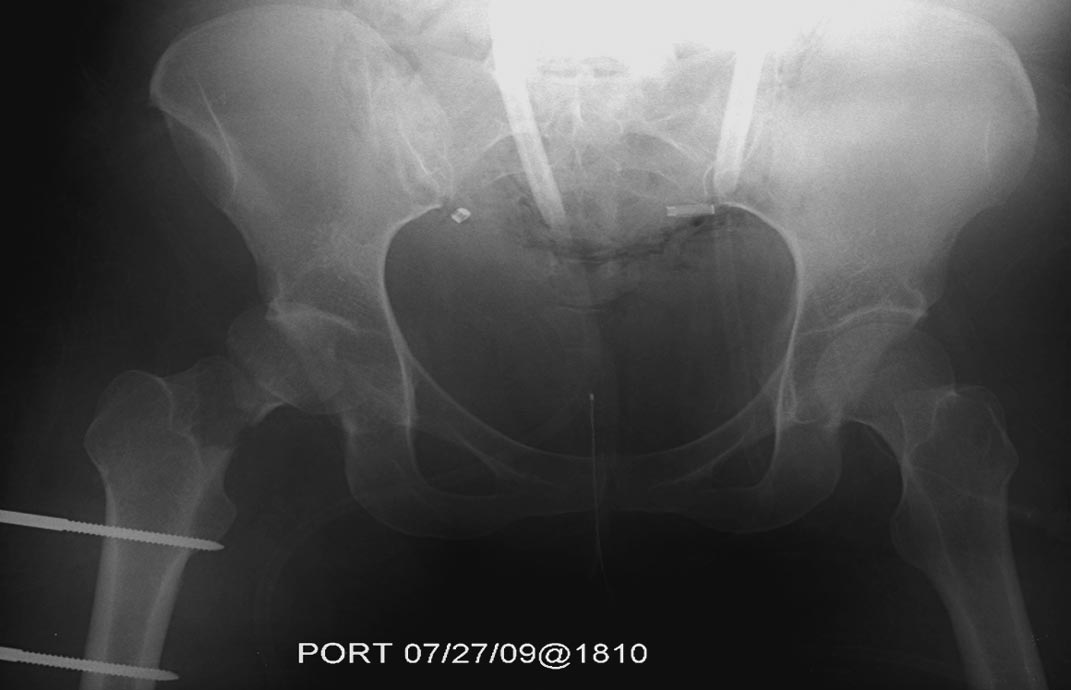

1.Вправление вывиха бедра, репозиция, остеосинтез перелома шейки бедра

В нашем случае с момента травмы прошло около 2 суток, и переломо-вывих

бедра остается не вправленный. По нашим данным, риск осложнений при

запоздалой репозиции остается высоким, и McKee 1998 также подтверждает,

что репозиция вывиха бедра после 6 часов приводит к осложнению

аваскулярным некрозом более чем 10%, а после 15.3 часов около 26%.

Во время совместной операции с хирургами по I&D  вакумированием раны

живота и ран конечности, смогли быстро наложить наружный фиксатор на бедро.